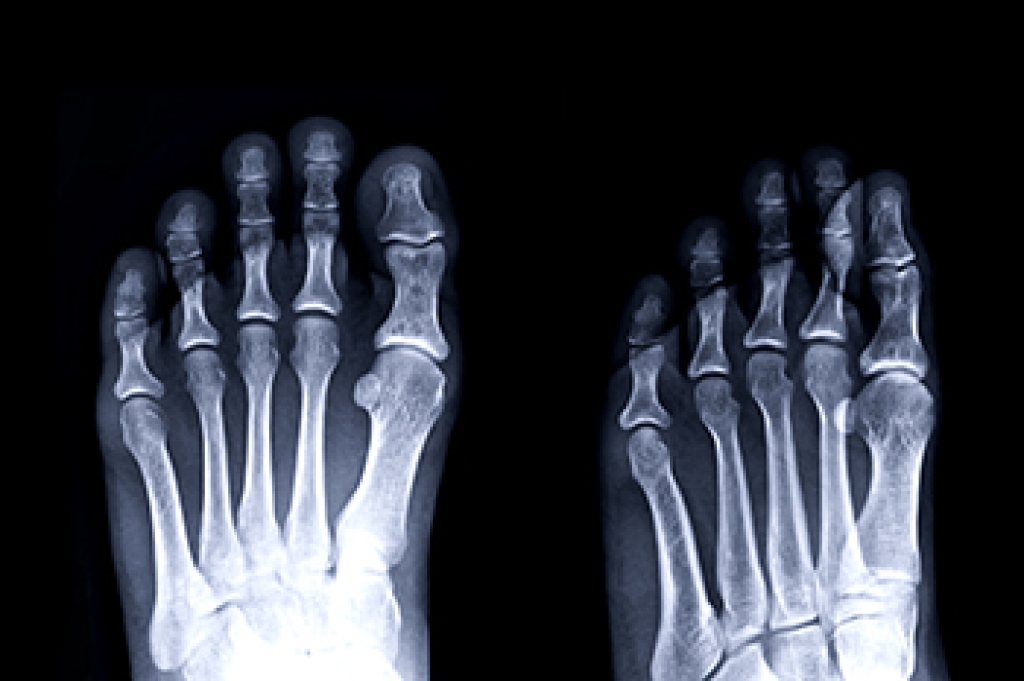

Sever’s disease is diagnosed by taking a thorough medical history and performing a physical examination. Imaging studies, such as an X-ray, can help rule out other injuries like a fracture.